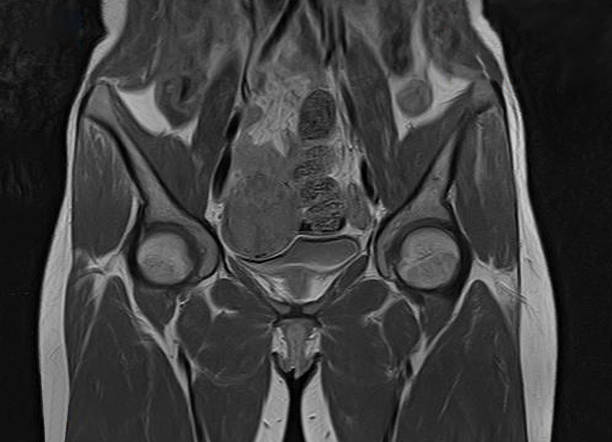

자궁근종은 자궁 내부나 외부에 발생하는 양성 종양으로, 자궁근육 내부에서 발생하는 경우가 가장 많습니다. 자궁근종은 여성들의 월경기에 더욱 빈번하게 발생하며, 대부분의 경우는 악성 종양으로 전이되지 않습니다.

자궁근종은 크기와 위치에 따라 다양한 증상을 일으키며, 일부 경우에는 생식기능에도 영향을 미칠 수 있습니다. 대개의 경우 자궁근종은 치료가 필요하지 않을 정도로 작고 증상이 없지만, 증상이 있거나 근종의 크기나 수가 많아지는 경우 치료가 필요할 수 있어 이번 시간에는 자궁근종 증상에 대해 자세히 알아보겠습니다.

자궁근종은 악성종양으로 전이되는 경우는 매우 드뭅니다. 그러나 자궁근종이 크거나 불규칙한 형태를 띄는 경우, 특히 빠르게 성장하거나 원래 크기보다 커진 경우에는 악성종양의 가능성을 염두에 두어야 합니다. 이러한 경우에는 추가적인 검사가 필요합니다.